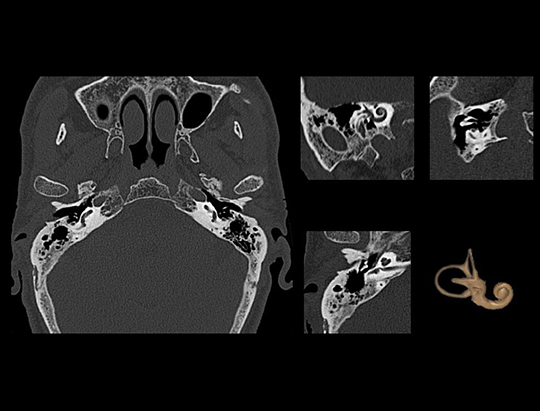

The large 24 cm axial digital PET field of view (FOV) provides exceptional image quality with 2.9 mm NEMA resolution that improves quantitative accuracy and small lesion detectability.

The data-driven head motion correction algorithm detects motion from list-mode data during patient scans and corrects motion blurring, accordingly, limiting the need to repeat scans.